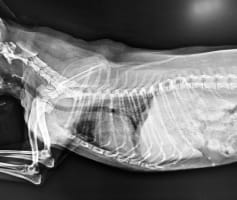

צילום רנטגן לכלב

צילום רנטגן לכלב מחיר

מחיר צילום רנטגן לכלב זה לא זול אבל שווה כל שקל לשמירת בריאות הכלב היקר לכם. במאמר הבא תמצאו את כל המידע מחיר צילום רנטגן לכלב, מה הוא כולל ולמה צריך לעשות צילום רנטגן לכלב מלכתחילה.